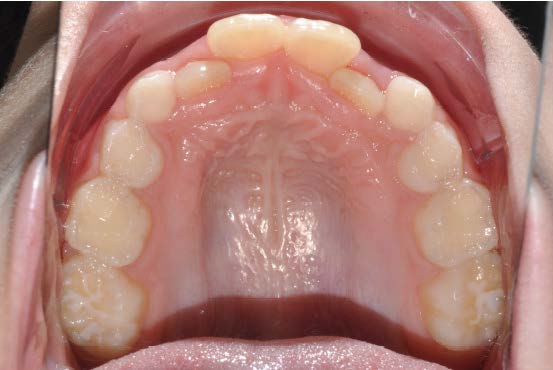

The patient presented with a skeletal Class I relationship and a mesofacial growth pattern, indicating balanced sagittal and vertical skeletal proportions. Dental examination revealed a Class I molar and canine relationship bilaterally. The patient was in the mixed dentition phase. Significant dental crowding was observed in both arches, consistent with a dentoalveolar discrepancy. Midline deviations were present, affecting dental symmetry and occlusal harmony. The maxillary lateral incisors were in crossbite, contributing to anterior transverse discrepancy and functional imbalance.

Periodontal evaluation revealed early signs of periodontal disease, primarily affecting tooth 41. Radiographic assessment demonstrated root convergence of teeth 11 and 21, indicating compromised root parallelism. Overall, the initial presentation was characterized by dentoalveolar crowding, transverse discrepancies, occlusal asymmetries, and early periodontal involvement within an otherwise favorable skeletal framework, requiring a carefully planned orthodontic approach to ensure functional stability and periodontal preservation.